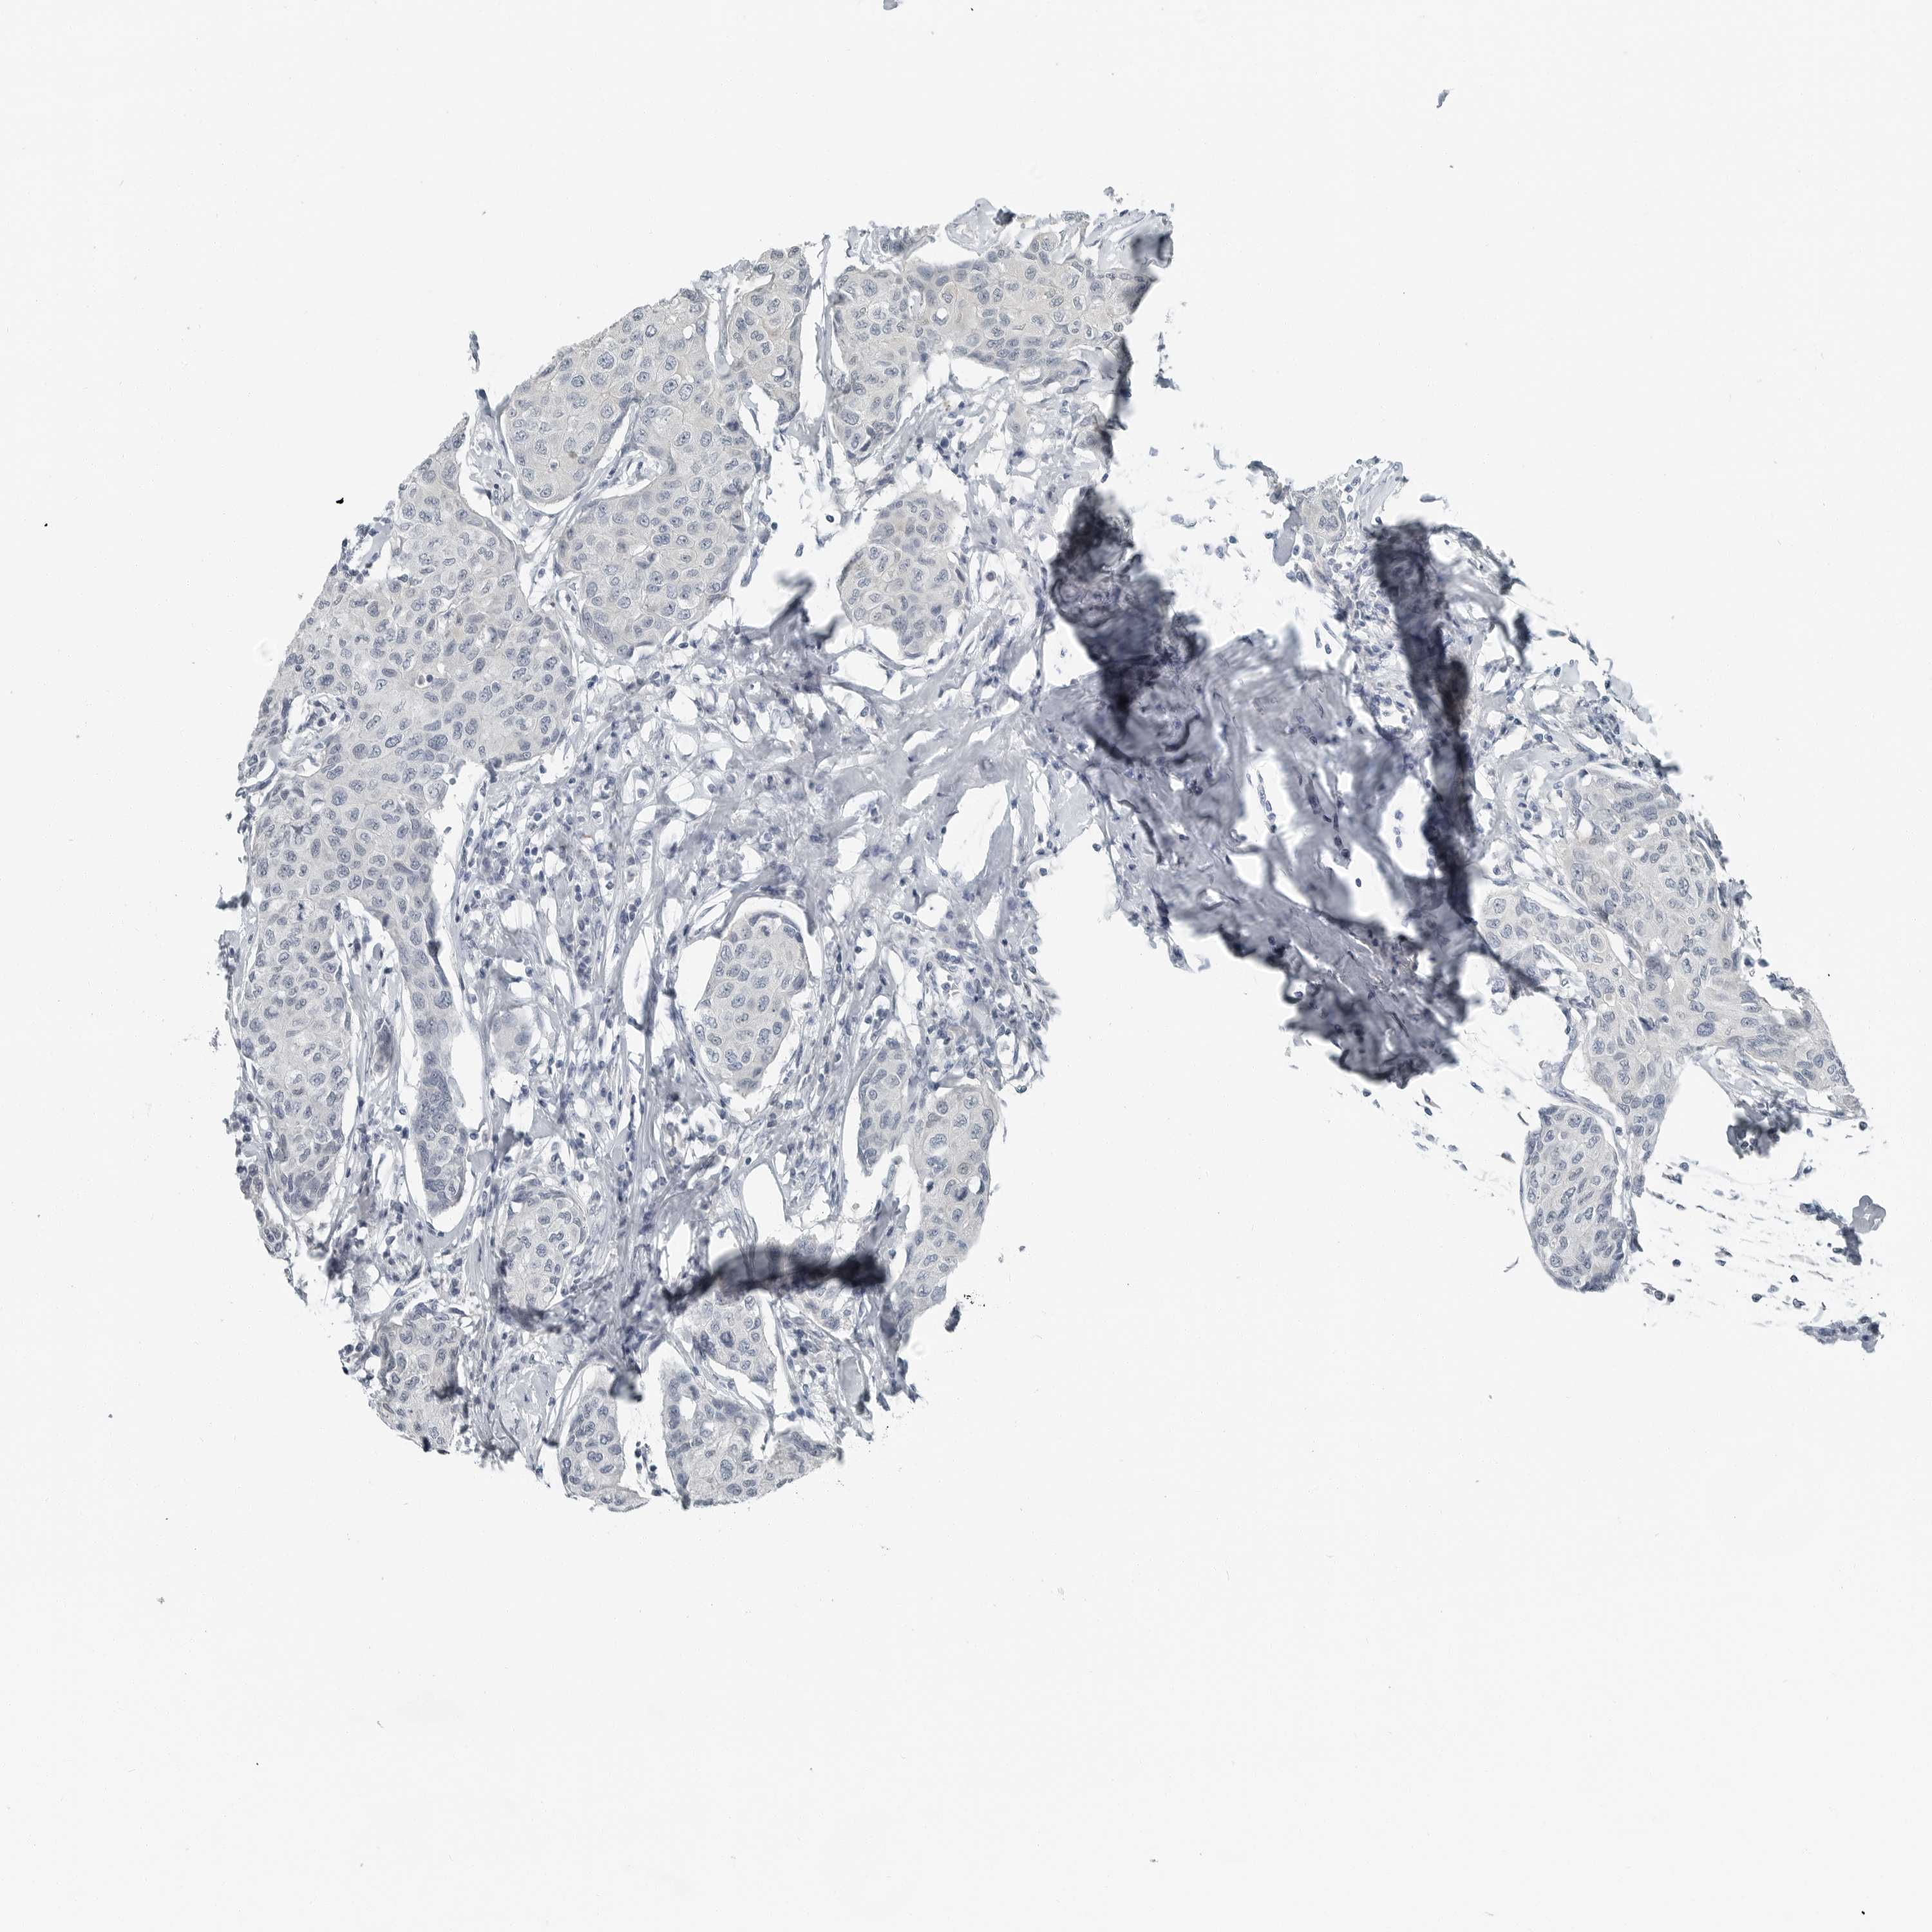

BRCA TCGA BRCA VALIDATION PROTEIN EXPRESSION

ANTIBODIES

AND

VALIDATION